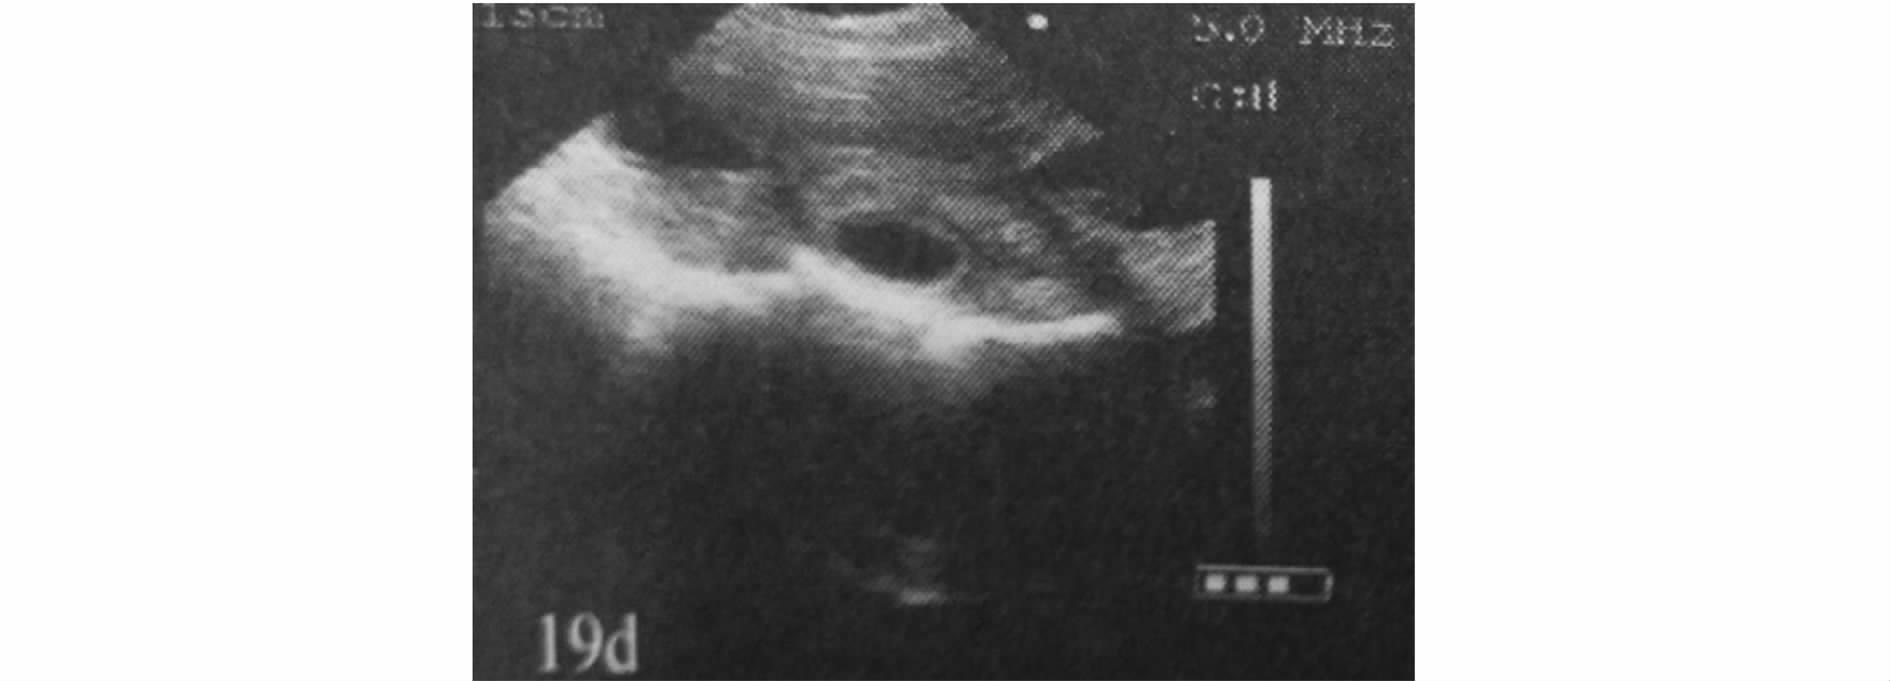

3.2.2 妊娠母猪 母猪妊娠的声像特征:妊娠初期子宫中出现孕囊,又称妊娠囊,内含初期胎水,量很少,对超声不产生反射,呈小的圆形暗区。在配种后19d、20d最早被扫查到时,暗区的直径在1.0cm左右,通常为一个暗区,有时可见2个或3个相邻的暗区(见图9),位于膀胱暗区的前下方或下方。为了便于B超操作者对B超成像进行有效准确地判断,作者专门附了一张母猪妊娠剖面与B超影像对比图(见图10)。

图9 母猪妊娠19日龄B超影像